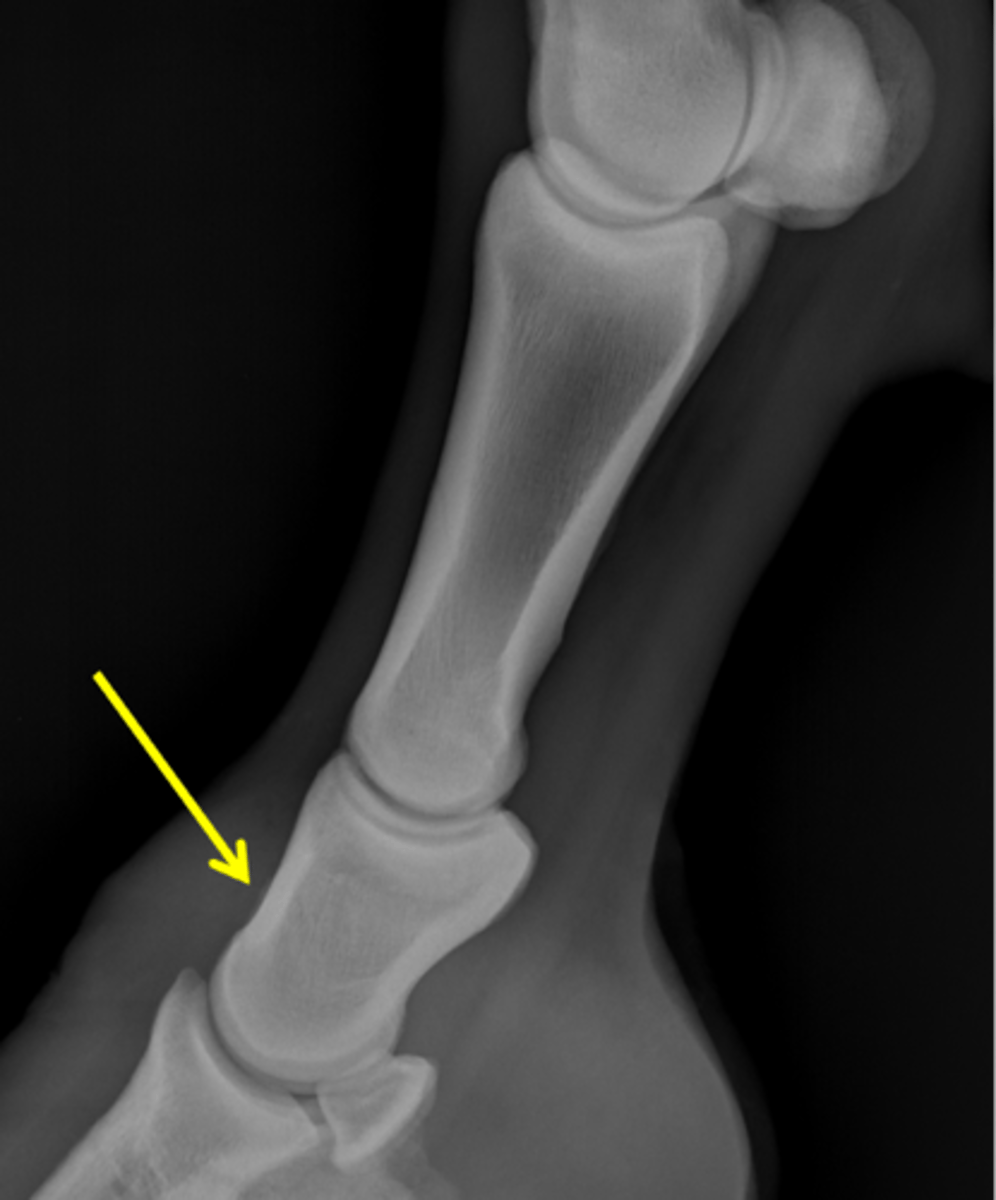

Short pastern (P2)

Upright pedal or high coronary

What view is this?

Short pastern (P2)

Long pastern (P1)

Long pastern (P1)

Short pastern (P2)

Medullary cavity

Ergot

Nutrient foramen of P2